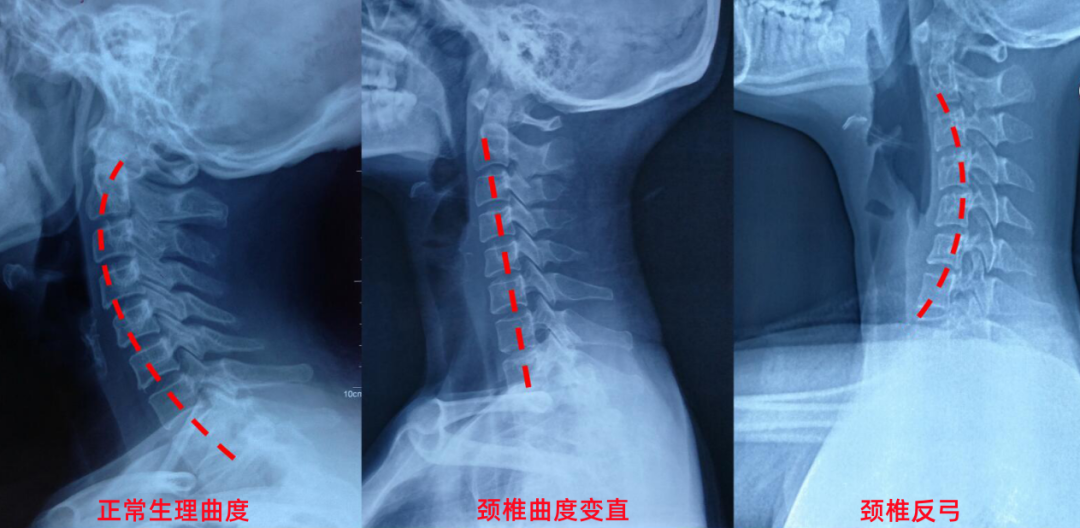

颈椎由7节椎体组成,正常呈向前凸的C形弧线。这个弧度能分散头部重量、缓冲压力,保护神经和血管。而颈椎生理曲度变直,是指这一弧度减小甚至消失,严重时可能反向弯曲即反弓。